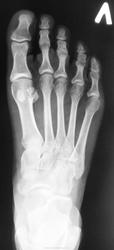

Молодая женщина. Беспокоят боли в ступнях по подошвенной поверхности, больше слева.

Правая стопа сделана больше для сравнения.

Остеохондропатия сесамовидной кости 1 пл/фал.сустава левой стопы.

несросшийся перелом сесамовидной слева